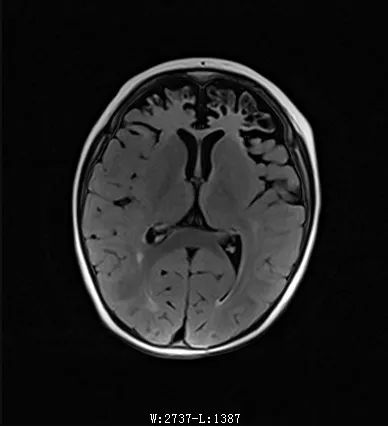

MRI:雙側(cè)額葉,雙側(cè)顳葉異常信號(hào)伴萎縮